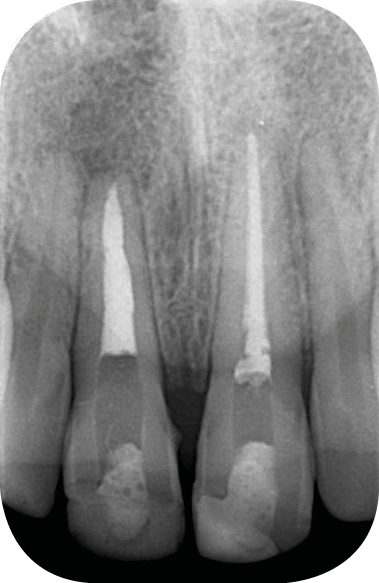

La discoloration de la dent dépulpée est due à trois causes principales :

– la nécrose, qui va donner une coloration plutôt brune [3] (fig. 1, 2) ;